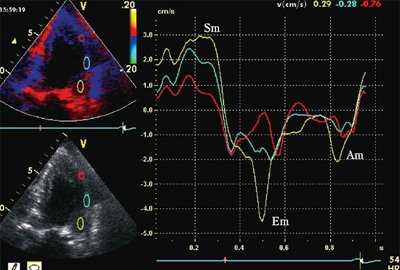

На рис. 3-5 приведены различные варианты ПСУ у больных с постинфарктным кардиосклерозом.

![Норма - формы кривых движения миокарда]()

![Седло - формы кривых движения миокарда с постинфарктным кардиосклерозом]()

б) При постинфарктном кардиосклерозе.

![Ступень - формы кривых движения миокарда с постинфарктным кардиосклерозом]()

в) При постинфарктном кардиосклерозе.

"Седловидная" и "ступенчатая" формы движения обусловлены наличием постсистолического смещения миокарда, превышающего по амплитуде максимальное систолическое смещение.